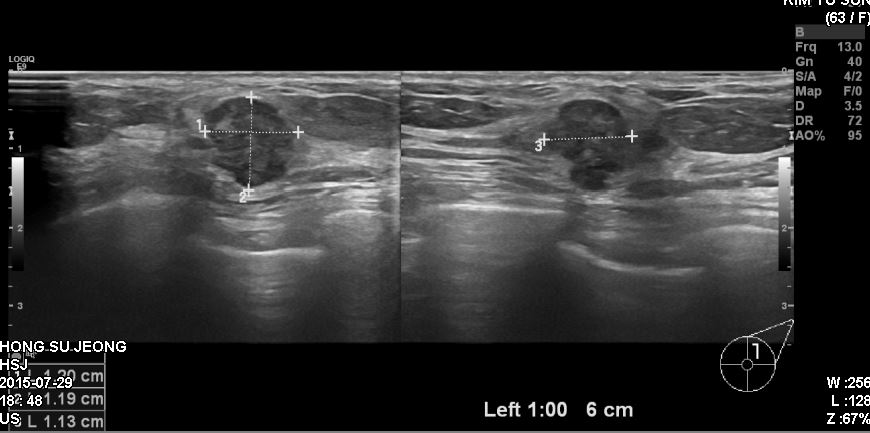

63세 여자분으로 건강검진상 이상소견보여 본원에서 초음파시행하고 조직검사 받은후

암진단받으셨습니다.